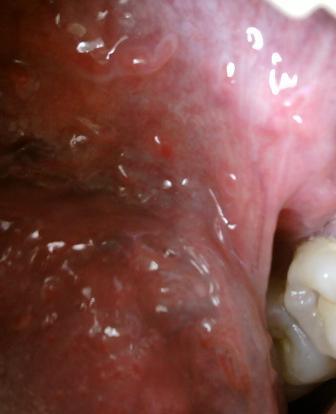

哪些尖锐湿疣适用于手术治疗目前医学上治疗尖锐湿疣的方法是比较多的,手术疗法就是其中一种,但是该疗法是比较适用于初期病情相对比较轻微的湿疣体的诊治,而对于中晚期比较严重的,则不建议采用,这是因为手术治疗期间,痛苦是比较大的,伤口恢复所需要的时间是比较久的,并且术后不注意护理,则复发的几率也会比较大。